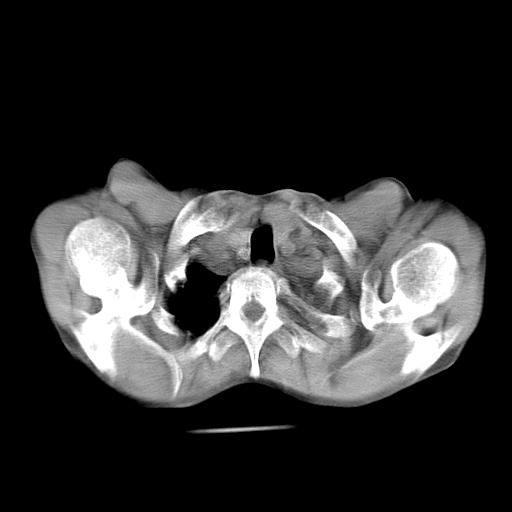

男  70岁,发烧咳嗽4天。盗汗,消瘦。无痰中带血丝,以前有肺tb病史,ct见,双肺tb,左侧胸廓塌陷,左胸膜肥厚粘连。纵隔移位,右侧胸腔积液,大家说说那个心影前左肺舌叶除了肺大炮还有炎症还是干酪性肺炎?有占位吗?我看纵隔淋巴结也大。

1)两肺继发性肺结核并左肺上叶肺不张,支气管扩张。2)双侧胸膜炎(胸膜增厚+少量胸腔积液)。

两肺继发性肺结核并感染,左肺上叶肺不张。建议ct增强。